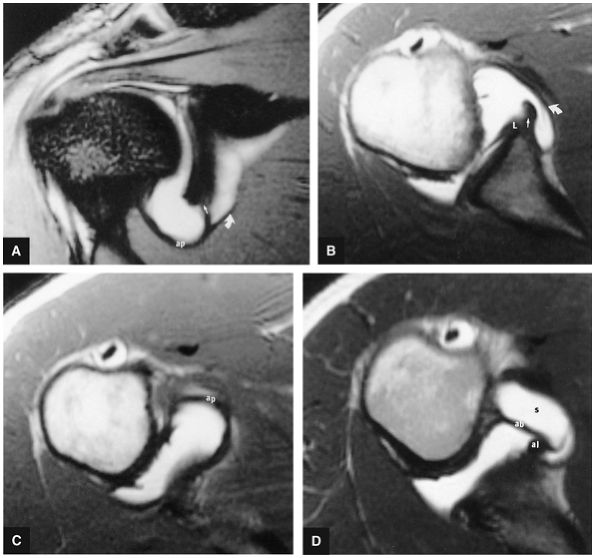

FIGURE 8.73 ● (A) The biceps origin can be located on a T2*-weighted coronal image. The glenoid origin of the long head of the biceps (b) is shown, as are the attachments to the anterior labrum (l) and superior glenoid (g). The biceps courses laterally and exits the joint between the supraspinatus (s) and subscapularis tendons. The axillary pouch (ap) of the IGHL is indicated. The tendon of the long head of the biceps enters the intertubercular groove under the transverse ligament. (B) Gross dissection demonstrates the anterior band (AB) and posterior band (PB) of the IGHL complex. This surgical view is from the perspective of viewing inferiorly into the axillary pouch. The anterior (A), posterior (P), and humeral head (HH) are indicated. Both the biceps tendon and posterior band contribute to the posterior labrum.

|